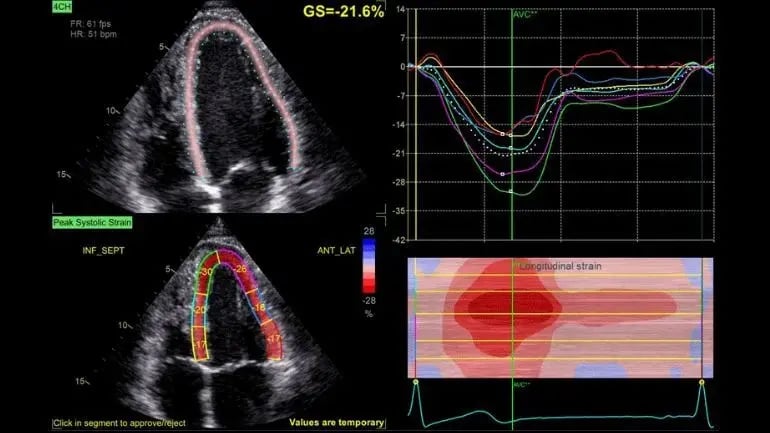

Ecocardiograma

Estudio de imagen que utiliza ultrasonido para evaluar la estructura y función del corazón en tiempo real.

Ecocardiograma 3D y 4D

- Ecocardiograma en reposo 2D, 3D, 4D, con strain rate, tisular, sincronía cardiaca.

- Ultrasonido Vivid 9 de GE con Strain Rate y sonda 4D Holter y MAPA Spacelabs y GE.